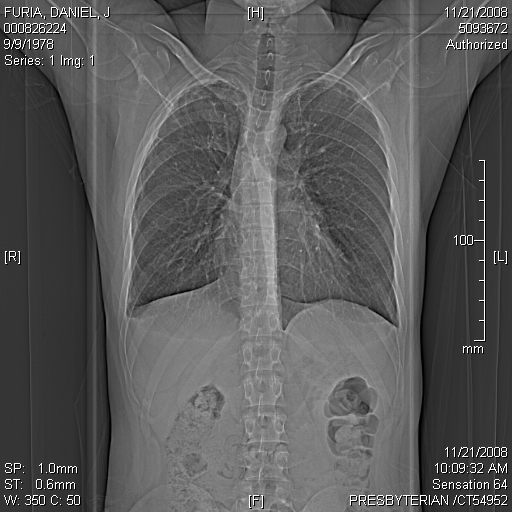

Some other CAT Scan Images I thought looked neat (healthy lung, not collapsed):